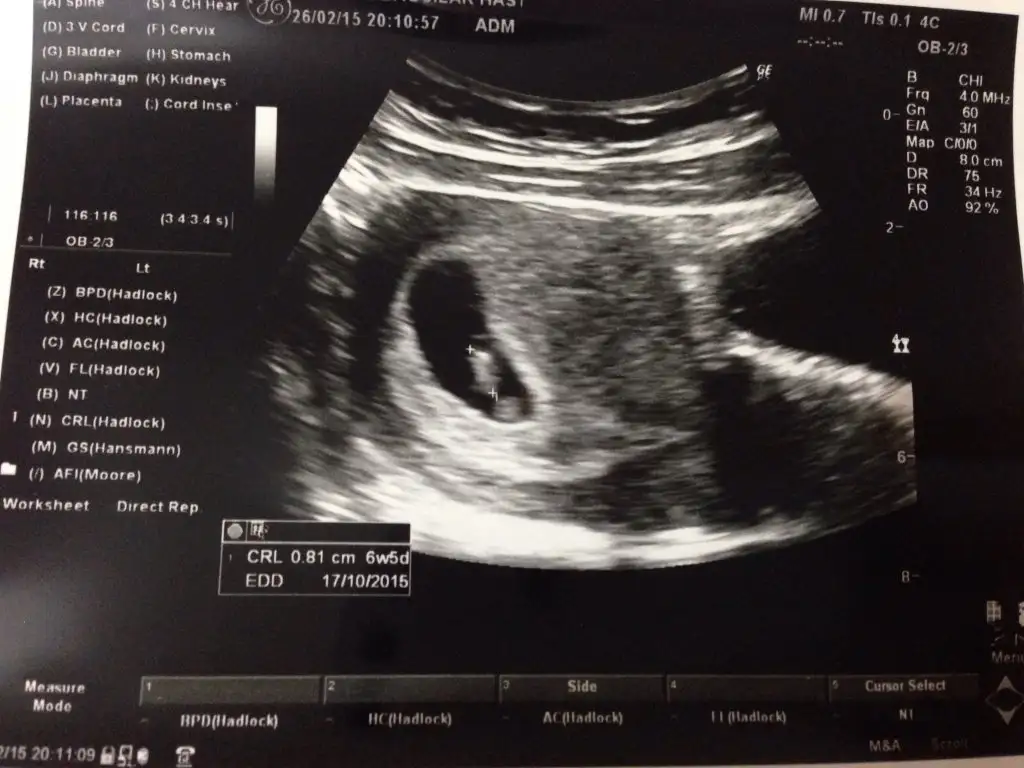

Burda tam 6+6. Bende anlamadim. Karindan ya da vajinal farkli oluyor diye okuyunca sastim kaldim. Ikinci hamileligim. Ilk bebegim erkekti. Ve o sagdaydi. O yuzden isin icinden cikamadim. Ikiside farkli olunca acaba cinsiyeti farkli mi diye dusundum. Baska yardimci olabilecek arkadaslar varsa cvp bekliyorum

arkadaşlar ben neler yaptım neler bir oğlum olsun diye ama tutturdum sonunda benimki iğneden sonraki 34. ve 36 . saat sonra 2 defa ilişki oldu ama sabah ilişkileri oldu bence ovulasyon olduğu gün veya ovulasyona en yakın dönemde ilişki olması gerekiyor bide sık ilişkinin bence bi mahsuru yok hızlı hareket eden y spermi daima hazır olmalı benimkide baştan beri usg resmine direk bakınca soldaydı